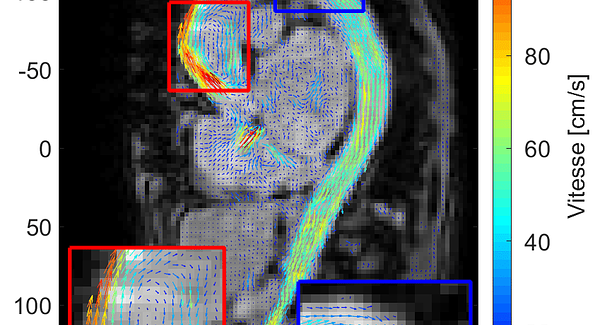

Nous proposons trois expériences: 1) La propagation d’une onde ultrasonore et ses interactions avec différents matériaux ; 2) La réalisation d’images avec un échographe médical pour deviner le contenu non visible et parfois surprenant de différents récipients ; 3) La visualisation du déplacement d’un fil pour comprendre ce qu’est l’effet Doppler.